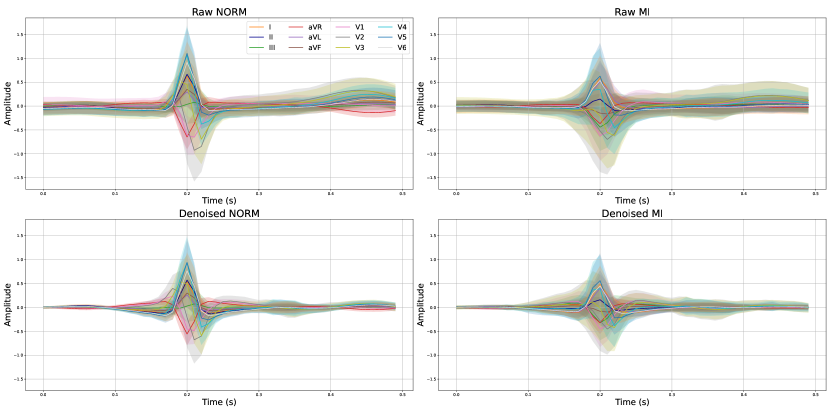

The Figure C.2 illustrates the distribution of raw and denoised signals across various leads for a selected beat within the population. It is important to note that individual investigations might encounter significant noise, and this figure serves as an example to showcase the substantial variance in beats across the population. Moreover, the figure visibly demonstrates the considerable discrepancy in signal amplitude values between the NORM and MI populations.